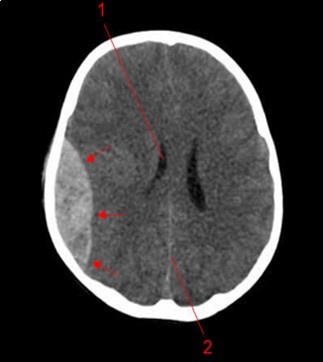

From the point of view of care, two (n=2) (10.52%) children received medical treatment compared to 17 (89.48%) children who received medical-surgical treatment. Neurosurgical treatment consisted of evacuation of the extra dural hematoma. This involved making a skin incision, trepanation (Figure 3 a), a preserved cranial bone flap, evacuation of the extra-dural haematoma (Figure 3 b), haemostasis either of the bone using bone wax or venous or arterial haemostasis by bipolar coagulation as appropriate, suspension of the dura mater (Figure 3 c), replacement of the bone flap (Figure 3 d) and finally suturing of the scalp in two planes. Figure 1, Figure 2, Figure 3.

Figure 1.Image of a brain CT scan without contrast, in a parenchymal window, axial view showing a right parietal extra dural hematoma associated with diffuse cerebral oedema, and subfalcorial brain schift

Image of a brain CT scan without contrast, in a parenchymal window, axial view showing a right parietal extra dural hematoma associated with diffuse cerebral oedema, and subfalcorial brain schift